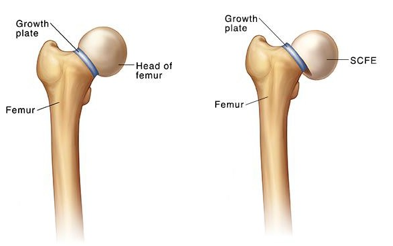

The bone in the thigh is called the femur. The top of the femur is shaped like a ball and is called the epiphysis. It fits into a cup shaped pocket in the pelvis. When the ball slips out of the pocket, it is called Slipped Capital Femoral Epiphysis (SCFE).

If the slip is severe, it can cause a lack of blood flow to the ball part of the thighbone. This can lead to permanent problems with hip movement. If left untreated, the ball can continue to slip.

This leads to decreased hip motion and increased joint stiffness and pain (degenerative joint disease).